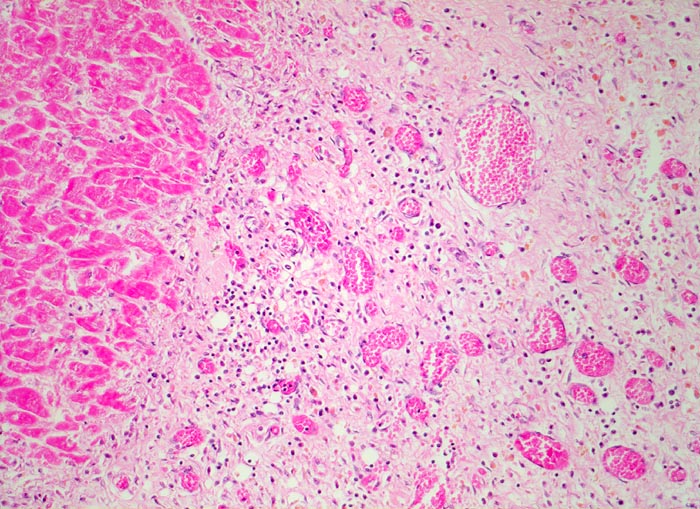

subakuter Myokardinfarkt

Das Granulationsgewebe rechts im Bild besteht aus lockerem Bindegewebe, Kapillaren und gemischtem Entzündungsinfiltrat. Die hämosiderinhaltigen Makrophagen sind an ihrer gelben Farbe erkennbar. Links im Bild die Koagulationsnekrose mit schollig zerfallenen hypereosinophilen Myokardfasern.

Ausgedehnter subakuter Myokardinfarkt von Hinterwand und Septum. Im Infarktrandbereich perakute Myokardnekrosen.

Narbengewebe kann ebenfalls vaskularisiert sein. Für die Diagnose eines subakuten Infarktes muss das Granulationsgewebe auch Entzündungszellen enthalten.